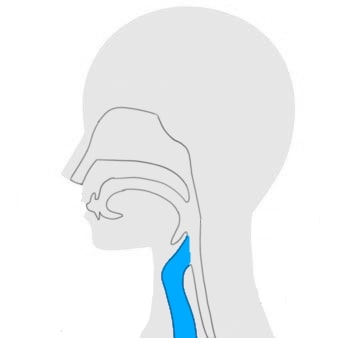

この治療法は、特定の薬剤と光を組み合わせてがん細胞を破壊するもので、口腔がんの治療にも適応できる可能性があります。

光免疫療法は、特定の波長の光を利用して、薬剤を活性化させることでがん細胞を攻撃します。

その後、特定の波長の光を当てることで、薬剤が活性化し、がん細胞を破壊することができます。